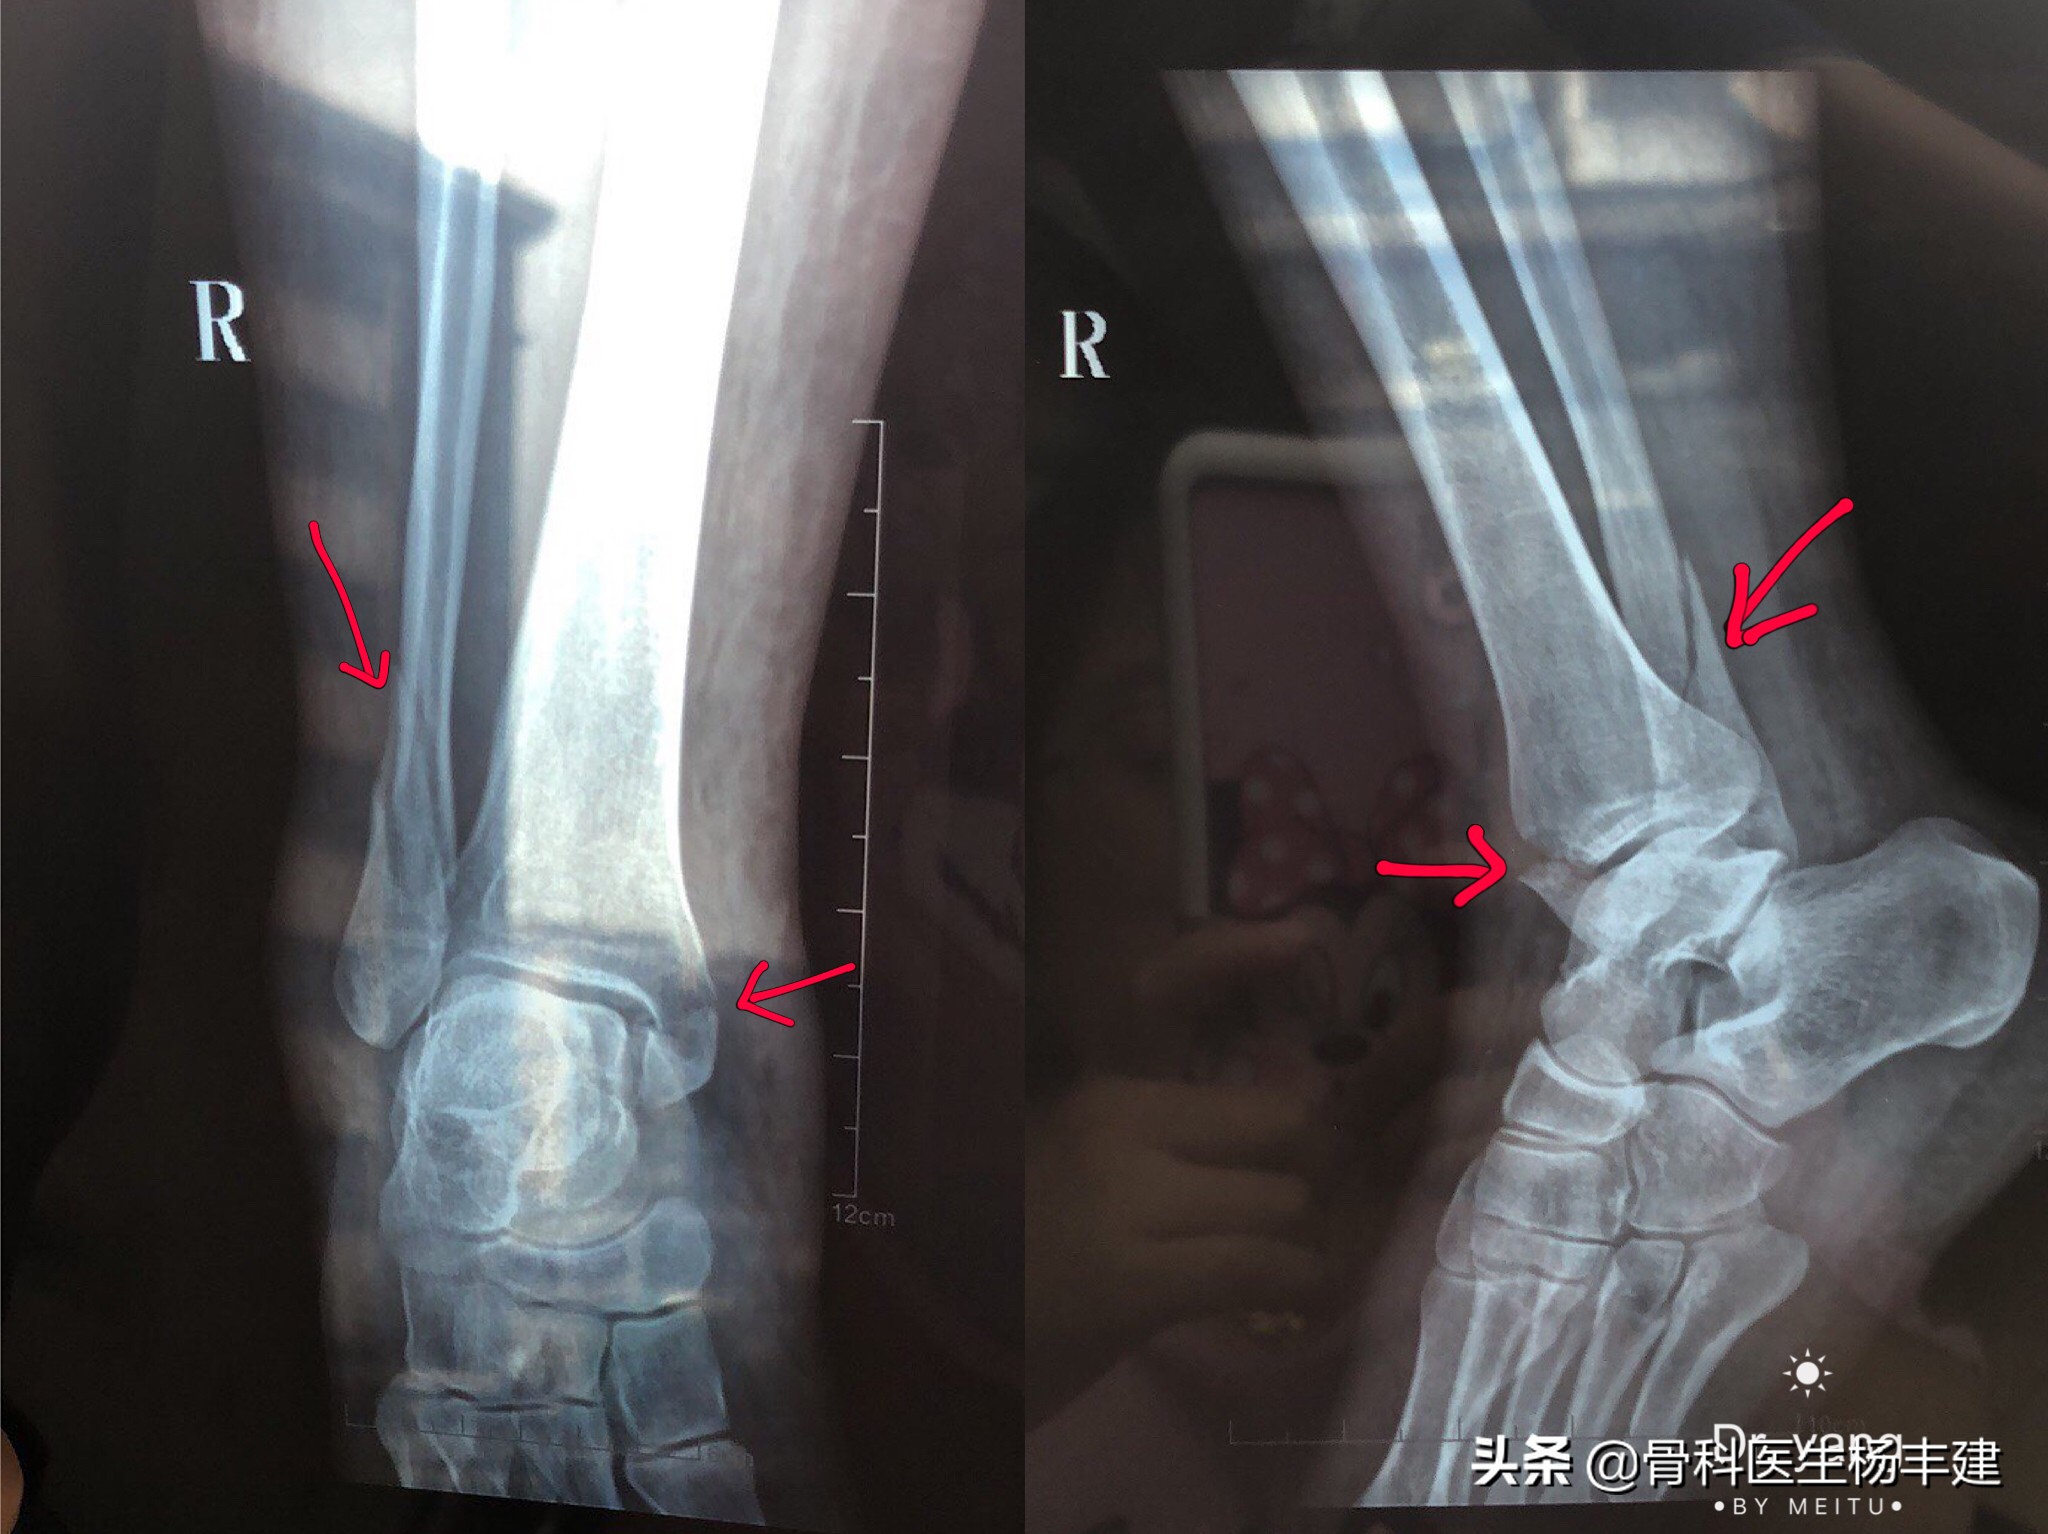

3,那么什么样的骨折需要做手术呢?如果损伤造成了两处,甚至两处以上的骨折(比如说内踝、外踝同时骨折,甚至连同后踝一起骨折),踝关节的稳定性往往会遭到破坏,从而出现比较明显的移位,这种情况是需要做手术治疗的。

内外踝均有骨折,并有明显移位,是手术治疗的指征

②骨折复位后,还需要关节下胫腓联合的宽度,以及踝穴两侧关节间隙的宽度。如果出现骨折完全复位,但是两侧关节间隙的宽度不对称,说明距骨的位置有问题,很可能存在下胫腓联合的脱位,也是需要修正的,通常使用螺丝钉收紧下胫腓联合。

手术前可见内侧踝穴明显增宽,距骨向外侧移位。手术中使用长螺钉收紧下胫腓联合,推挤距骨归位。